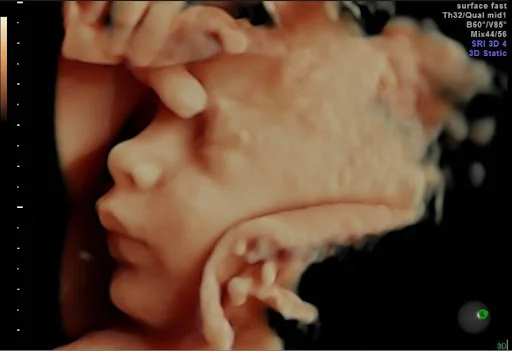

Experimente a emoçãode conhecer o rostinhodo seu bebê antes donascimento!

Tenha acesso a ultrassonografias detalhadas realizadas com tecnologias de última geração que monitoram a sua saúde e a do bebê ao longo de toda a gestação.

Imagens 3D e 5D

Permitem que você viva a experiência de acompanhar os movimentos e o desenvolvimento do bebê em tempo real, como seus gestos, expressões e características físicas, criando memórias inestimáveis.